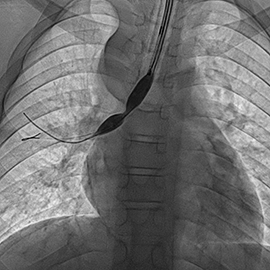

Blood samples indicated possible abnormalities and a follow-up X-ray and CT (computed tomography) scan revealed granulomas (small areas of inflammation) in his lungs. Doctors diagnosed Ja’ir with a rare autoimmune disease called granulomatosis with polyangiitis (GPA), which most commonly affects the sinuses, lungs and kidneys.